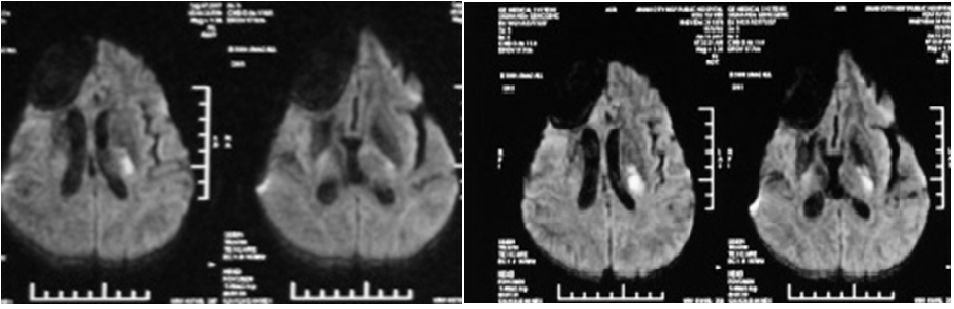

從基礎到應用——MMSE、MoCA量表的使用,知多少?導讀簡易精神狀態(tài)量表(MMSE)與蒙特利爾認知評估量表(MoCA量表)是目前臨床上應用最廣泛的認知功能篩查量表,主要用于各種類型的認知障礙和癡呆的初步篩查。但兩種認知評估量表具有各自不同的優(yōu)缺點。本文以病例為引導,介紹了MMSE、MoCA的主要特點及評定中的注意事項。病例概要寇XX,男,42歲,右利手,是一名骨科醫(yī)生,因“反應遲鈍、記憶力減退、少語1月余”于2017年9月28日入院。2004年因右側(cè)額葉膠質(zhì)細胞瘤行手術(shù)治療及放療;治療后患者一直上班,工作、生活無影響。2015年膠質(zhì)細胞瘤復發(fā),再次行手術(shù)治療,仍未影響生活與工作。2016年3月份再次行放療治療,治療后正常工作、生活。2017年6月份因“言語不清、右側(cè)肢體無力”就診于縣級醫(yī)院,診斷為急性腦梗塞,住院治療后,遺留睡眠多、右側(cè)肢體活動欠靈活。家屬回憶,患者6月份腦梗塞后,就存在輕度的記憶力下降的情況,但基本不影響生活、工作。偶爾開處方時會用錯藥物。2017年6月與9月顱腦MR2017年6月與9月顱腦MR2017-09-28第一次來我院治療。2017-10-23來我院門診復查。2017-12-07第二次來我院認知康復治療。2018-01-15第三次來我院行認知康復治療。檢查結(jié)果如下:問題思考基于上述病例簡介,思考以下問題:1.患者MMSE、MoCA經(jīng)治療后分值正常,但家屬訴患者仍反應遲鈍,記憶力差,懶散,無主動性,不能上班。2.患者MMSE、MoCA分值正常,但ADL分值增加,基本日常生活能力下降???3.MMSE及MoCA同一患者重復評測出現(xiàn)假陰性。4.MMSE及MoCA評定的缺點及注意事項有哪些?5.遇到這種情況怎么辦?是否需要別的量表復測。簡易精神狀態(tài)量表(MMSE)概述MMSE(mini-mentalstateexaminiation)中文名“簡易精神狀態(tài)量表”,內(nèi)容簡練,共六個方面,共30個小題,測定時間短5-10分鐘,易被老人接受,是癡呆篩選的首選量表。該量表由Folstein編制于1975年,是使用最廣泛的認知障礙篩選工具之一,評分易受到文化程度影響。主要用于癡呆的篩查和評估。MMSE量表的條目(共6個方面30小題)MMSE量表優(yōu)缺點補充方案小結(jié)?MMSE以總分為分析指標,不能把單項分值視為相應的認知功能表現(xiàn)。?評價分數(shù)受到年齡和教育的影響,文化程度較高的老年人可能有假陰性,文化程度低的可能出現(xiàn)假陽性。?受語言的影響大,操方言者可能會出現(xiàn)假陽性。?語言測查的項目較多,主要對測查左側(cè)大腦半球病變所致的認知功能障礙較敏感,而對額葉及右半球病變所致的認知功能障礙不敏。MMSE在評估額顳葉癡呆患者中的效力特別微弱。?MMSE在鑒定早期癡呆,特別是輕度認知損傷方面較差。蒙特利爾認知評估量表(MoCA量表)概述蒙特利爾認知評估量表(MoCA量表,MontrealCognitiveAssessment)是一個用來對認知功能障礙進行快速篩查的評定工具。耗時約15分鐘。該量表目前已被翻譯成多種語言,我國流行的版本有北京版、北京-廣州版(普通話版)、長沙版、粵語版、香港版和臺灣版。MoCA量表條目MoCA量表的優(yōu)缺點MoCA量表對各種原因(如血管因素、腦炎、帕金森病、輕度AD)導致的MCI都較敏感,敏感度明顯高于MMSE。補充方案小結(jié)?MoCA量表同樣也會受到教育程度的影響,文化背景的差異、檢查者使用MoCA的技巧和經(jīng)驗,檢查的環(huán)境及被試的情緒及精神狀態(tài)等均會對MoCA的分值產(chǎn)生影響。?MoCA只能作為MCI和AD診斷的篩查工具,對癡呆的病因診斷方面作用有限,MoCA用于癡呆療效的評定尚有待于進一步評價。?MoCA量表的不足主要體現(xiàn)在相較MMSE題目變復雜而帶來的地板效應。?檢測認知功能損害的最早期階段,MoCA量表可能比MMSE量表更合適。MoCA與MMSE的比較MMSE與MoCA評定注意事項環(huán)境準備?安靜、舒適,并盡可能保證以后的測試在相同的環(huán)境中進行?房間中不能有受訪者可看到的鐘表、日歷等,最好使用“請勿打擾”標志?不應讓受訪者看到你對他的評分人物準備?建立良好的關系?備物齊全(鉛筆、手表、紙張等)?鼓勵受訪者完成測試,提供眼鏡/助聽器?給予正性的反饋?應盡量避免搜集任何關于不良事件的信息最初的交談?開始前進行5分鐘左右的交談,話題是中性的,比如天氣、最近發(fā)生的事情等?注意:避免談到受訪者的健康、負性的、有壓力的事情測試中注意事項?不應使受訪者感到要求的回答速度過快?每個測試項目只允許嘗試1次?受訪者的反應不正確,測試者應開始下一個項目的檢查?給予受訪者的反饋應當是中性的,而且通常不應當指出受訪者的反應是對還是不對?評價恰當?受訪者特意詢問自己是否做對了,可以給予反饋盡量取得受訪者合作?同受訪者的交流要保持平靜、前后一致和簡明扼要?不要讓受訪者的焦慮或憤怒導致對抗?如果受訪者仍然不合作,那么測試者應當暫時停止測試其它注意事項?向被試者直接詢問?可以由照料者陪伴以緩解緊張?注意避免傷害老人的自尊心問題分析介紹了這么多,對于前文中的問題大家心中是否已經(jīng)有了答案?快來一起看看吧~1.患者3個半月內(nèi)評定4次MMSE及MoCA,評定過于頻繁,出現(xiàn)假陰性。2.患者學歷高,骨科主治醫(yī)師,學習能力強,存在學習效應。3.患者家屬照顧的過于周到,患者的康復能力、鍛煉能力受到影響,基本的穿衣、洗漱、吃飯等都是家人照顧。4.雖然MMSE及MoCA分值恢復正常,但患者的ADL評分增高,客觀說明患者癡呆程度加重。5.當患者需要重復評測時,應至少間隔3個月評定一次,或者換用其他量表進行評測。(CASI,ACE-R,CDR,GDS)